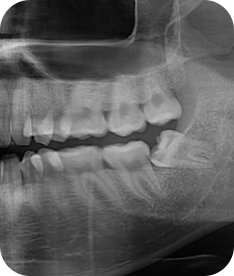

청담네오플란트는 3D CT 촬영 후 전문의료진들의 정확한 분석으로 안전하게 사랑니를 발치합니다.

청담네오플란트치과 사랑니 발치 프로세스

01. CT 촬영

안전하고 통증을 최소화한 발치를 위해 3차원 정밀 분석을 합니다.

02. 정확한 분석

사랑니의 크기와 방향, 깊이, 뿌리 상태 등과 구강검진을 실시합니다.